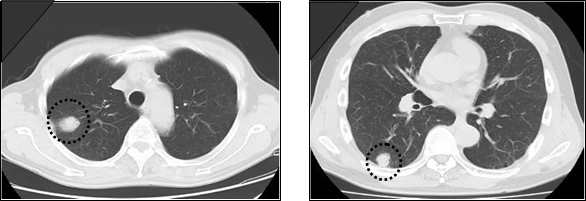

当センターの肺ドックで発見された肺がん

CT画像